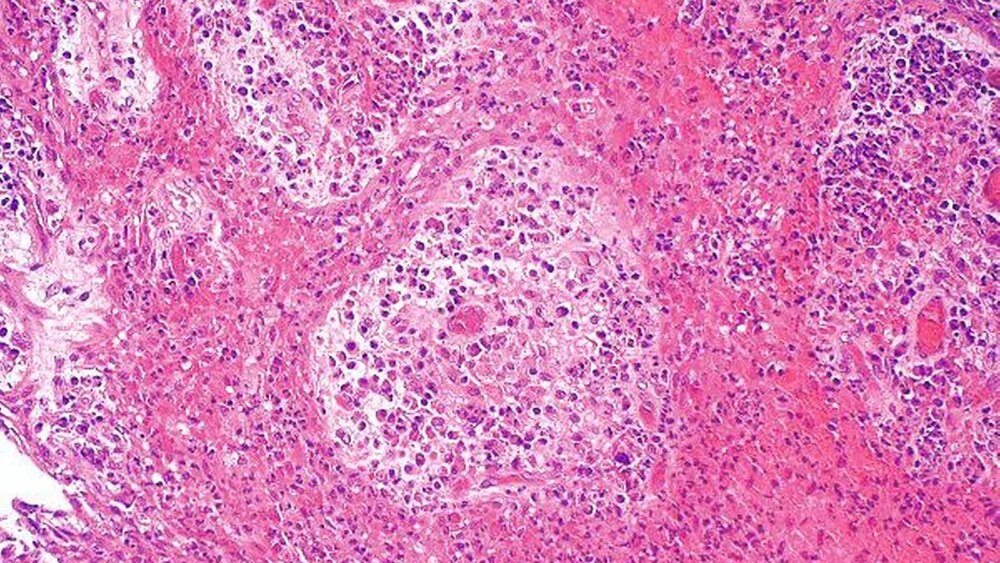

Die pathohistologische Untersuchung erbrachte die Diagnose einer radikulären Zyste (Abbildungen 4 und 5).

Die radikuläre Zyste ist eine entzündlich bedingte, in der Regel periapikal gelegene odontogene Zyste, die durch Proliferation der Malassez’schen Epithelreste, Reste der Hertwig-Epithelscheide oder seltener des Saumepitheles in ein apikales Granulom hinein gekennzeichnet ist [Regezi JA et al., 2003]. Die radikuläre Zyste ist mit 85 Prozent die am häufigsten vorkommende odontogene Zyste und kommt im Oberkiefer etwa doppelt so häufig zu liegen, wie im Unterkiefer [Tortorici S et al., 2007]. Radiologisch stellen sich radikuläre Zysten meist als relativ scharf begrenzte Aufhellungen mit Randsklerose dar.

Differentialdiagnostisch ist neben der follikulären Zyste, die sich durch ein perikoronales Wachstum an retinierten Zähnen, zum Beispiel in absteigender Häufigkeit an Weisheitszähnen, Eckzähnen und seltener an Prämolaren, auszeichnet, an Keratozysten oder odontogene Tumoren, wie das Ameloblastom, zu denken [Walter C., Kunkel M., 2005; Neville et al., 2001] . In seltenen Fällen wird sogar über die Entstehung eines Plattenepithelkarzinomes in einer radikulären Zyste berichtet. Aus diesem Grund sollte das bei der Operation gewonnene Gewebe pathologisch untersucht werden.